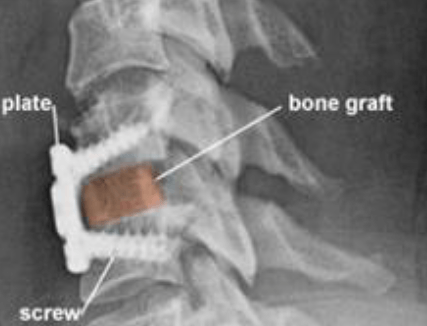

After the disc is removed, the space between the bony vertebrae is empty. To prevent the vertebrae from collapsing and rubbing together, a spacer bone graft is inserted to fill the open disc space. The graft serves as a bridge between the two vertebrae to create a spinal fusion. The bone graft and vertebrae are fixed in place with metal plates and screws. Following surgery the body begins its natural healing process and new bone cells grow around the graft. After 3 to 6 months, the bone graft should join the two vertebrae and form one solid piece of bone. The instrumentation and fusion work together, similar to reinforced concrete.

Figure 5. (side view) A bone graft is shaped and inserted into the shelf space between the vertebrae. The bone graft is often reinforced with a metal plate screwed into the vertebrae to provide stability during fusion. An x-ray is taken to verify the position of the graft, plate, and screws (Fig. 6).

Figure 6. X-ray and illustration showing a metal plate and four screws used to hold the bone graft between the vertebrae while fusion occurs.